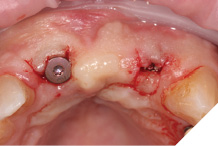

A larger healing abutment was placed on the UR1 fixture to allow further healing but to prevent the risk of losing buccal keratinized mucosa a smaller healing abutment was used on the UL2. Which meant at 3 weeks later when we came to fit the provisional bridge, we had to re-expose the fixture head. We also used a small 3mm soft tissue biopsy punch on the UL2 site to widen the initial emergence profile and allow passive fit of the provisional bridge. The model was socket by 1mm to allow the pontic site to be developed and allow modification of the profile (Figs. 25-28).

Fig. 25

Fig. 26

Fig. 27

Fig. 28